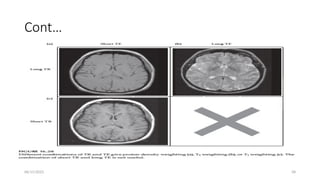

Spin Echo Image Contrast

• At short TRs, there is not enough time for full T1 relaxation,

• so that Mz is reduced when the next excitation pulse is applied.

• At these short TRs, there is more contrast—signal difference—between tissues,

than at long TRs.

• However, the signal is also reduced. We call this effect ‘saturation’.

• At long TRs there is time for complete relaxation of T1.

• If TE is short, there is little time for T2 relaxation & Mxy will be close to its

starting value

• at longer TEs, T2 decay reduces height of the echo, w/c means reduced SNR.

• However, there is also most contrast b/n different tissues, with fluids (long T2)

staying bright.

• There are four possible combinations of TR and TE, but only three are useful .